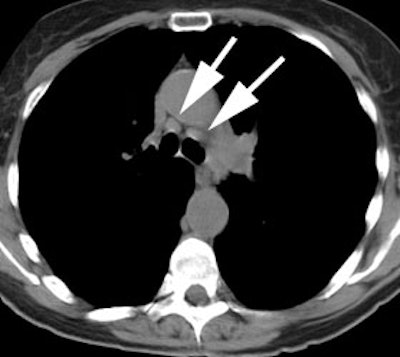

Example: This patient with a left lung non-small cell lung cancer demonstrated a pathologic aorto-pulmonary window node (N2) by CT size criteria (white arrow), and a non-pathologic retrocaval-pretracheal contralateral mediastinal node (N3) (yellow arrow). PET-FDG images revealed increased tracer accumulation within both nodes, consistent with metastases. (Case courtesy of H. Page McAdams MD, Department of Radiology, Duke University Medical Center)

A central cancer near the aortopulmonary

window, as in this case, is difficult to separate from

possible mediastinal lymph nodes. |